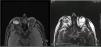

Por sus antecedentes personales y características de las pruebas complementarias como ecografía o resonancia, la opción diagnóstica más probable era metástasis de adenocarcinoma de próstata, certificándose posteriormente con los resultados anatomopatológicos.

Due to his personal history and results of the complementary tests such as ultrasound and magnetic resonance, the most likely diagnostic option was metastasis of prostate carcinoma, subsequently being confirmed with the histopathology results.